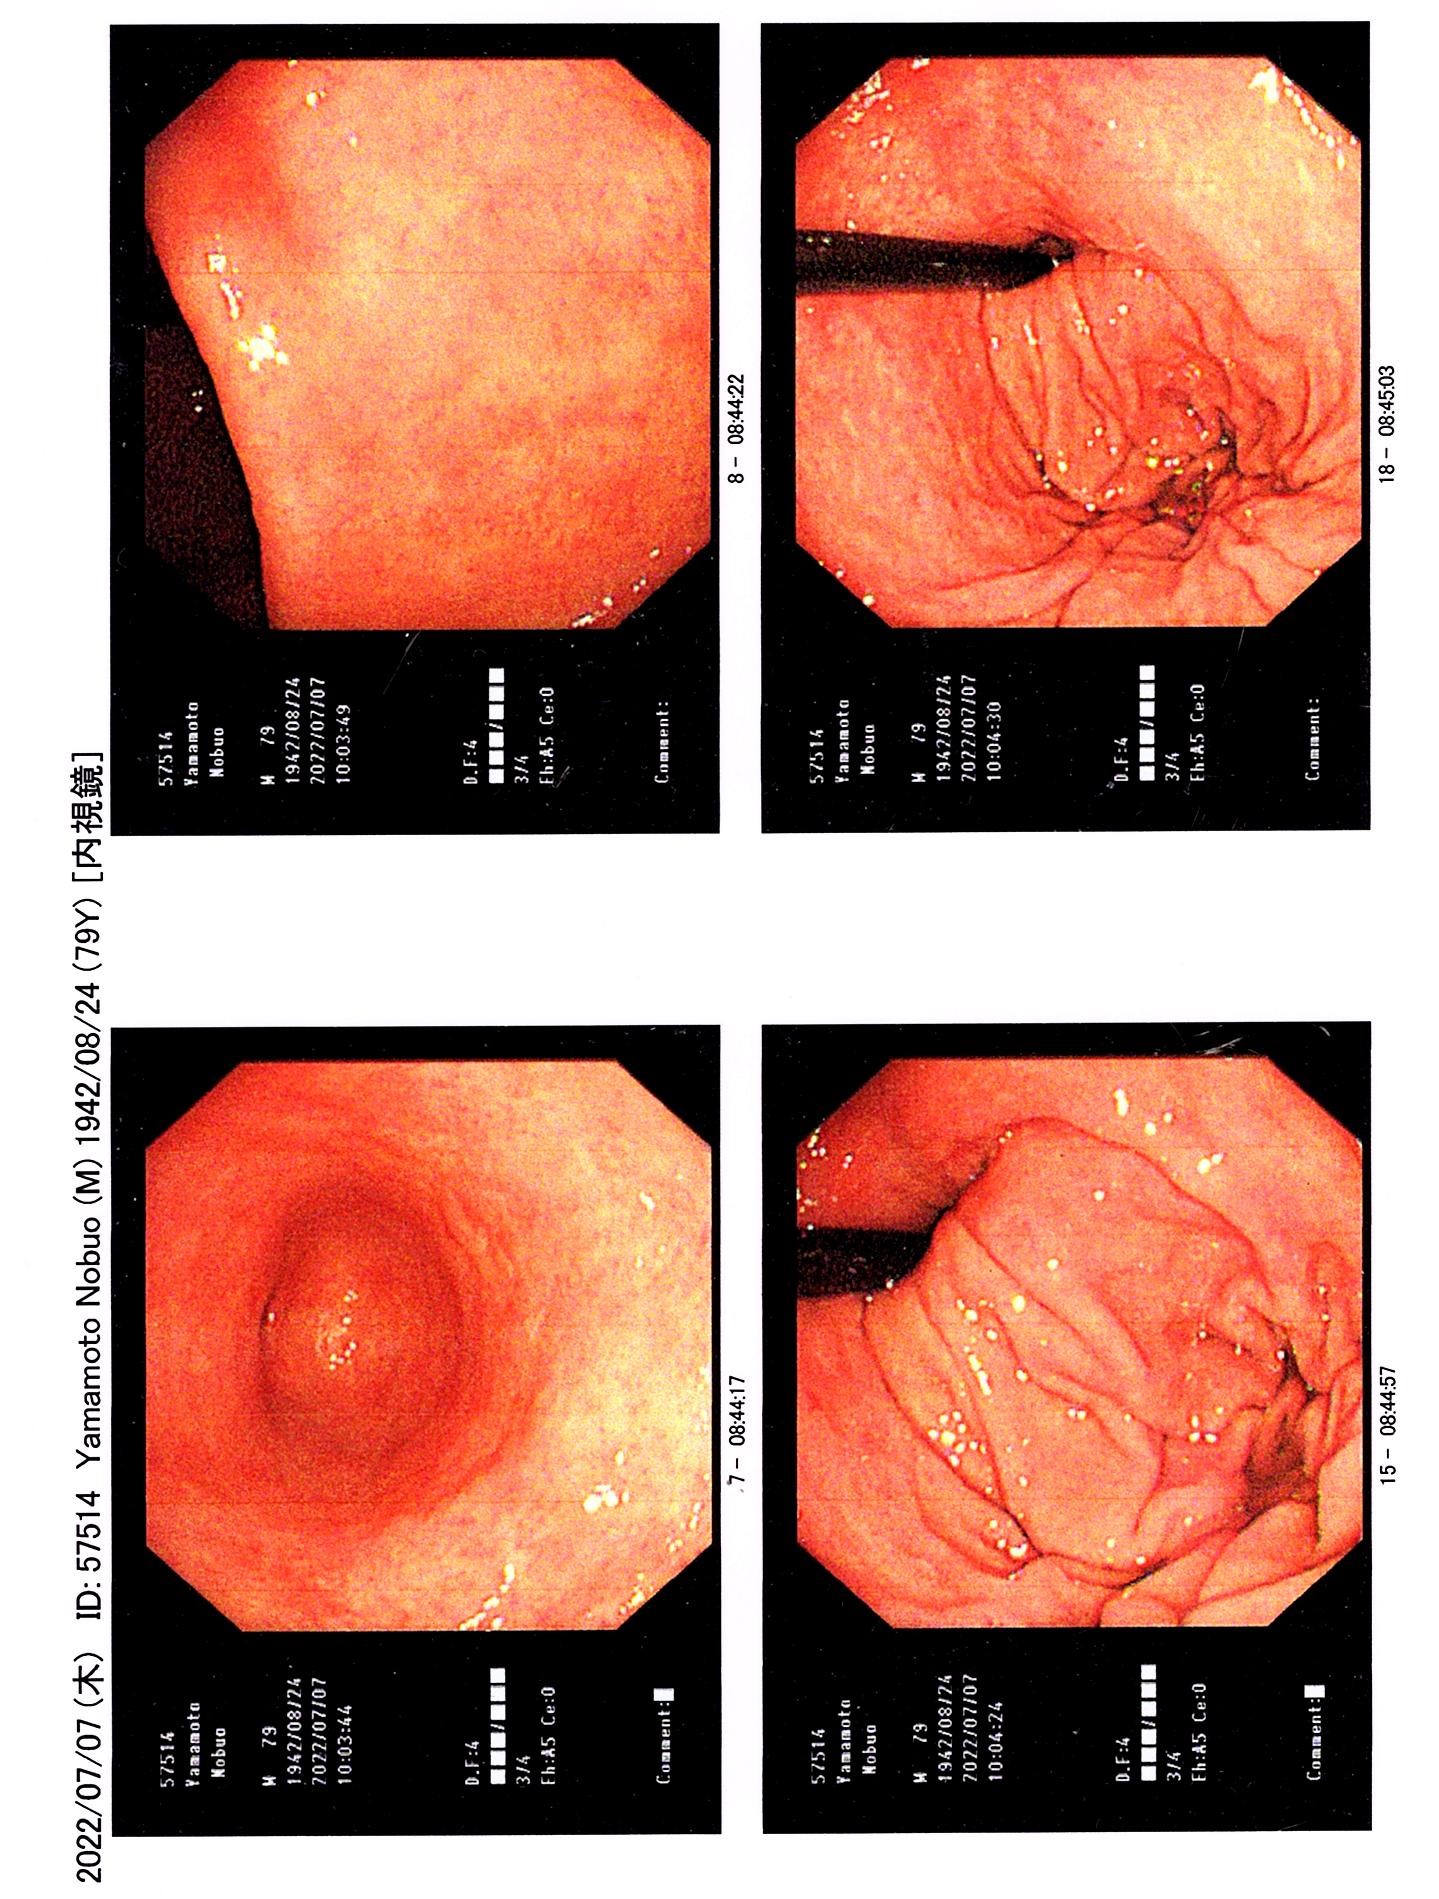

僕の胃の内視鏡写真(異常なし)

2014年8月1日(金)

そこで、2014年8月1日(金)8時に山口内科クリニックに行き、今度は胃の内視鏡検査を受ける。 その結果は異常なしであった。一安心。胃のカラー写真を先生から頂く。この写真が右上の画像です。 このクリニックに隣接する薬局で、1週間分のピロリ菌除菌の薬をもらい、この日の夕食にピロリ菌除菌の薬を1回目として飲む。

胃の内視鏡写真(異常なし)

2022年7月7日(木)

2022年7月7日(木)にも山口内科クリニックで、山口先生に内視鏡による胃検診をして頂きました。結果は右の写真の通り、胃がんは認められませんでした。